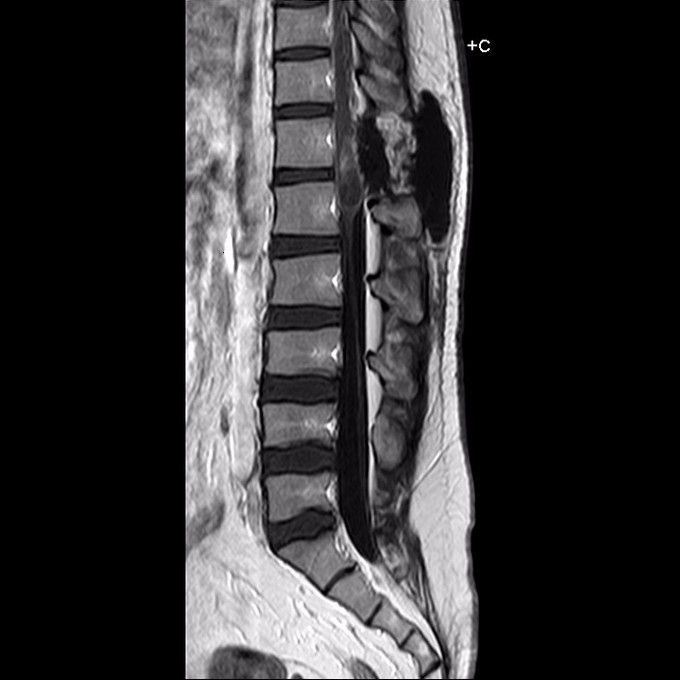

26岁,男性。患者3月前无明确诱因出现足底麻木,行走有“踩棉花”感,无双下肢疼痛,无腰骶部皮肤异常,无排便功能障碍、无双下肢畸形,无间歇性跛行等不适,无低热、盗汗及乏力等症状,后逐渐出现右下肢外侧皮肤感觉迟钝、麻木,康复锻炼数月症状无明显缓解,行腰椎MRI提示“胸12-腰1水平椎管内占位病变”。发病以来,患者精神、食欲可,睡眠一般,小解稍困难,大便正常,体重未见明显减轻。

术前考虑畸胎瘤、脂肪瘤、皮样囊肿等可能。充分准备后手术切除肿瘤,术中发现圆锥部位张力较高,打开硬脊膜,镜下见硬膜下、脊髓内肿瘤,为黄色脂肪样组织,质地稍韧,血供一般,包膜完整,厚且韧,与脊髓粘连严重。考虑脂肪瘤。先沿包膜内切除肿瘤,小心分离包膜与脊髓的粘连。小部分粘连过于紧密,无法完全分离,予双极电凝至无血供。严密缝合硬脊膜。留置硬膜外引流管1条。